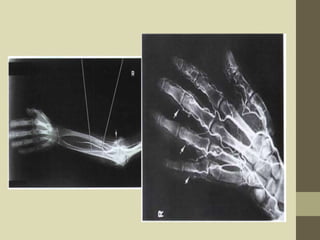

Upper limb angiography

• Radiological study of

arterial system

supplying the upper

limbs by the retrograde

introduction of contrast

media through the

femoral artery.

Filming

• Generally, true AP projections are taken with the

arms extended and hand supinated

• Hand arteriograms are obtained in supine or

prone arm positions

• Injections and imaging system depends on the

equipment used

• A representative program for a rapid imaging

system may be two films per second for 5

seconds followed by one per second for 5

seconds.